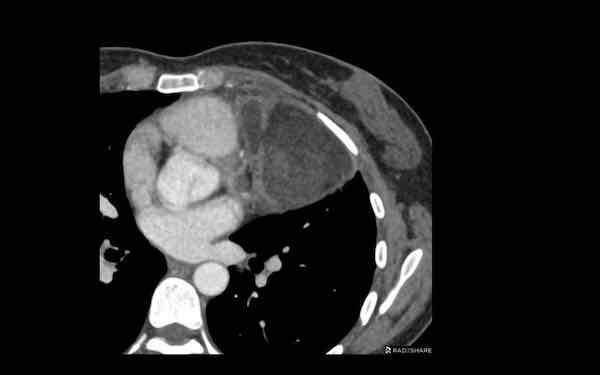

Các hình ảnh này của một bệnh nhân nam 68 tuổi, vừa trải qua phẫu thuật bắc cầu động mạch vành.

Bệnh nhân than phiền khó thở.

Nồng độ D-dimer cao và CT được thực hiện để tìm kiếm thuyên tắc phổi.

Hình ảnh

Có một khối trong trung thất trước mạch máu.

Tỷ trọng là 44